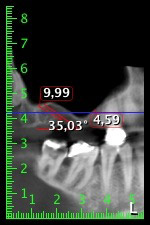

To restrict the augmentation to region 14, and in consultation with the patient, it was planned that implant 16 would be placed, inclined, in the dorso-cranial direction (Fig. 8).

This method requires a screw-retained solution for the final restoration. An angled abutment (e.g. 35°) was required so the screw could be perpendicular to the occlusion plane, which allowed the bridge to be attached occlusally.

Image 8: DVT with plan of insertion angle for implant 16